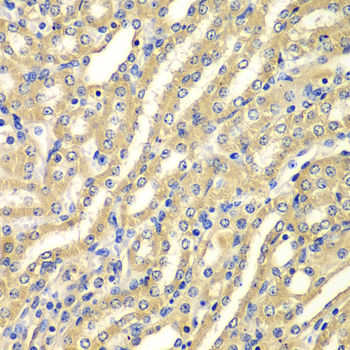

• A7537: image 2

Immunohistochemistry of paraffin-embedded human kidney using WIPI2 antibody at dilution of 1:100 (x400 lens).